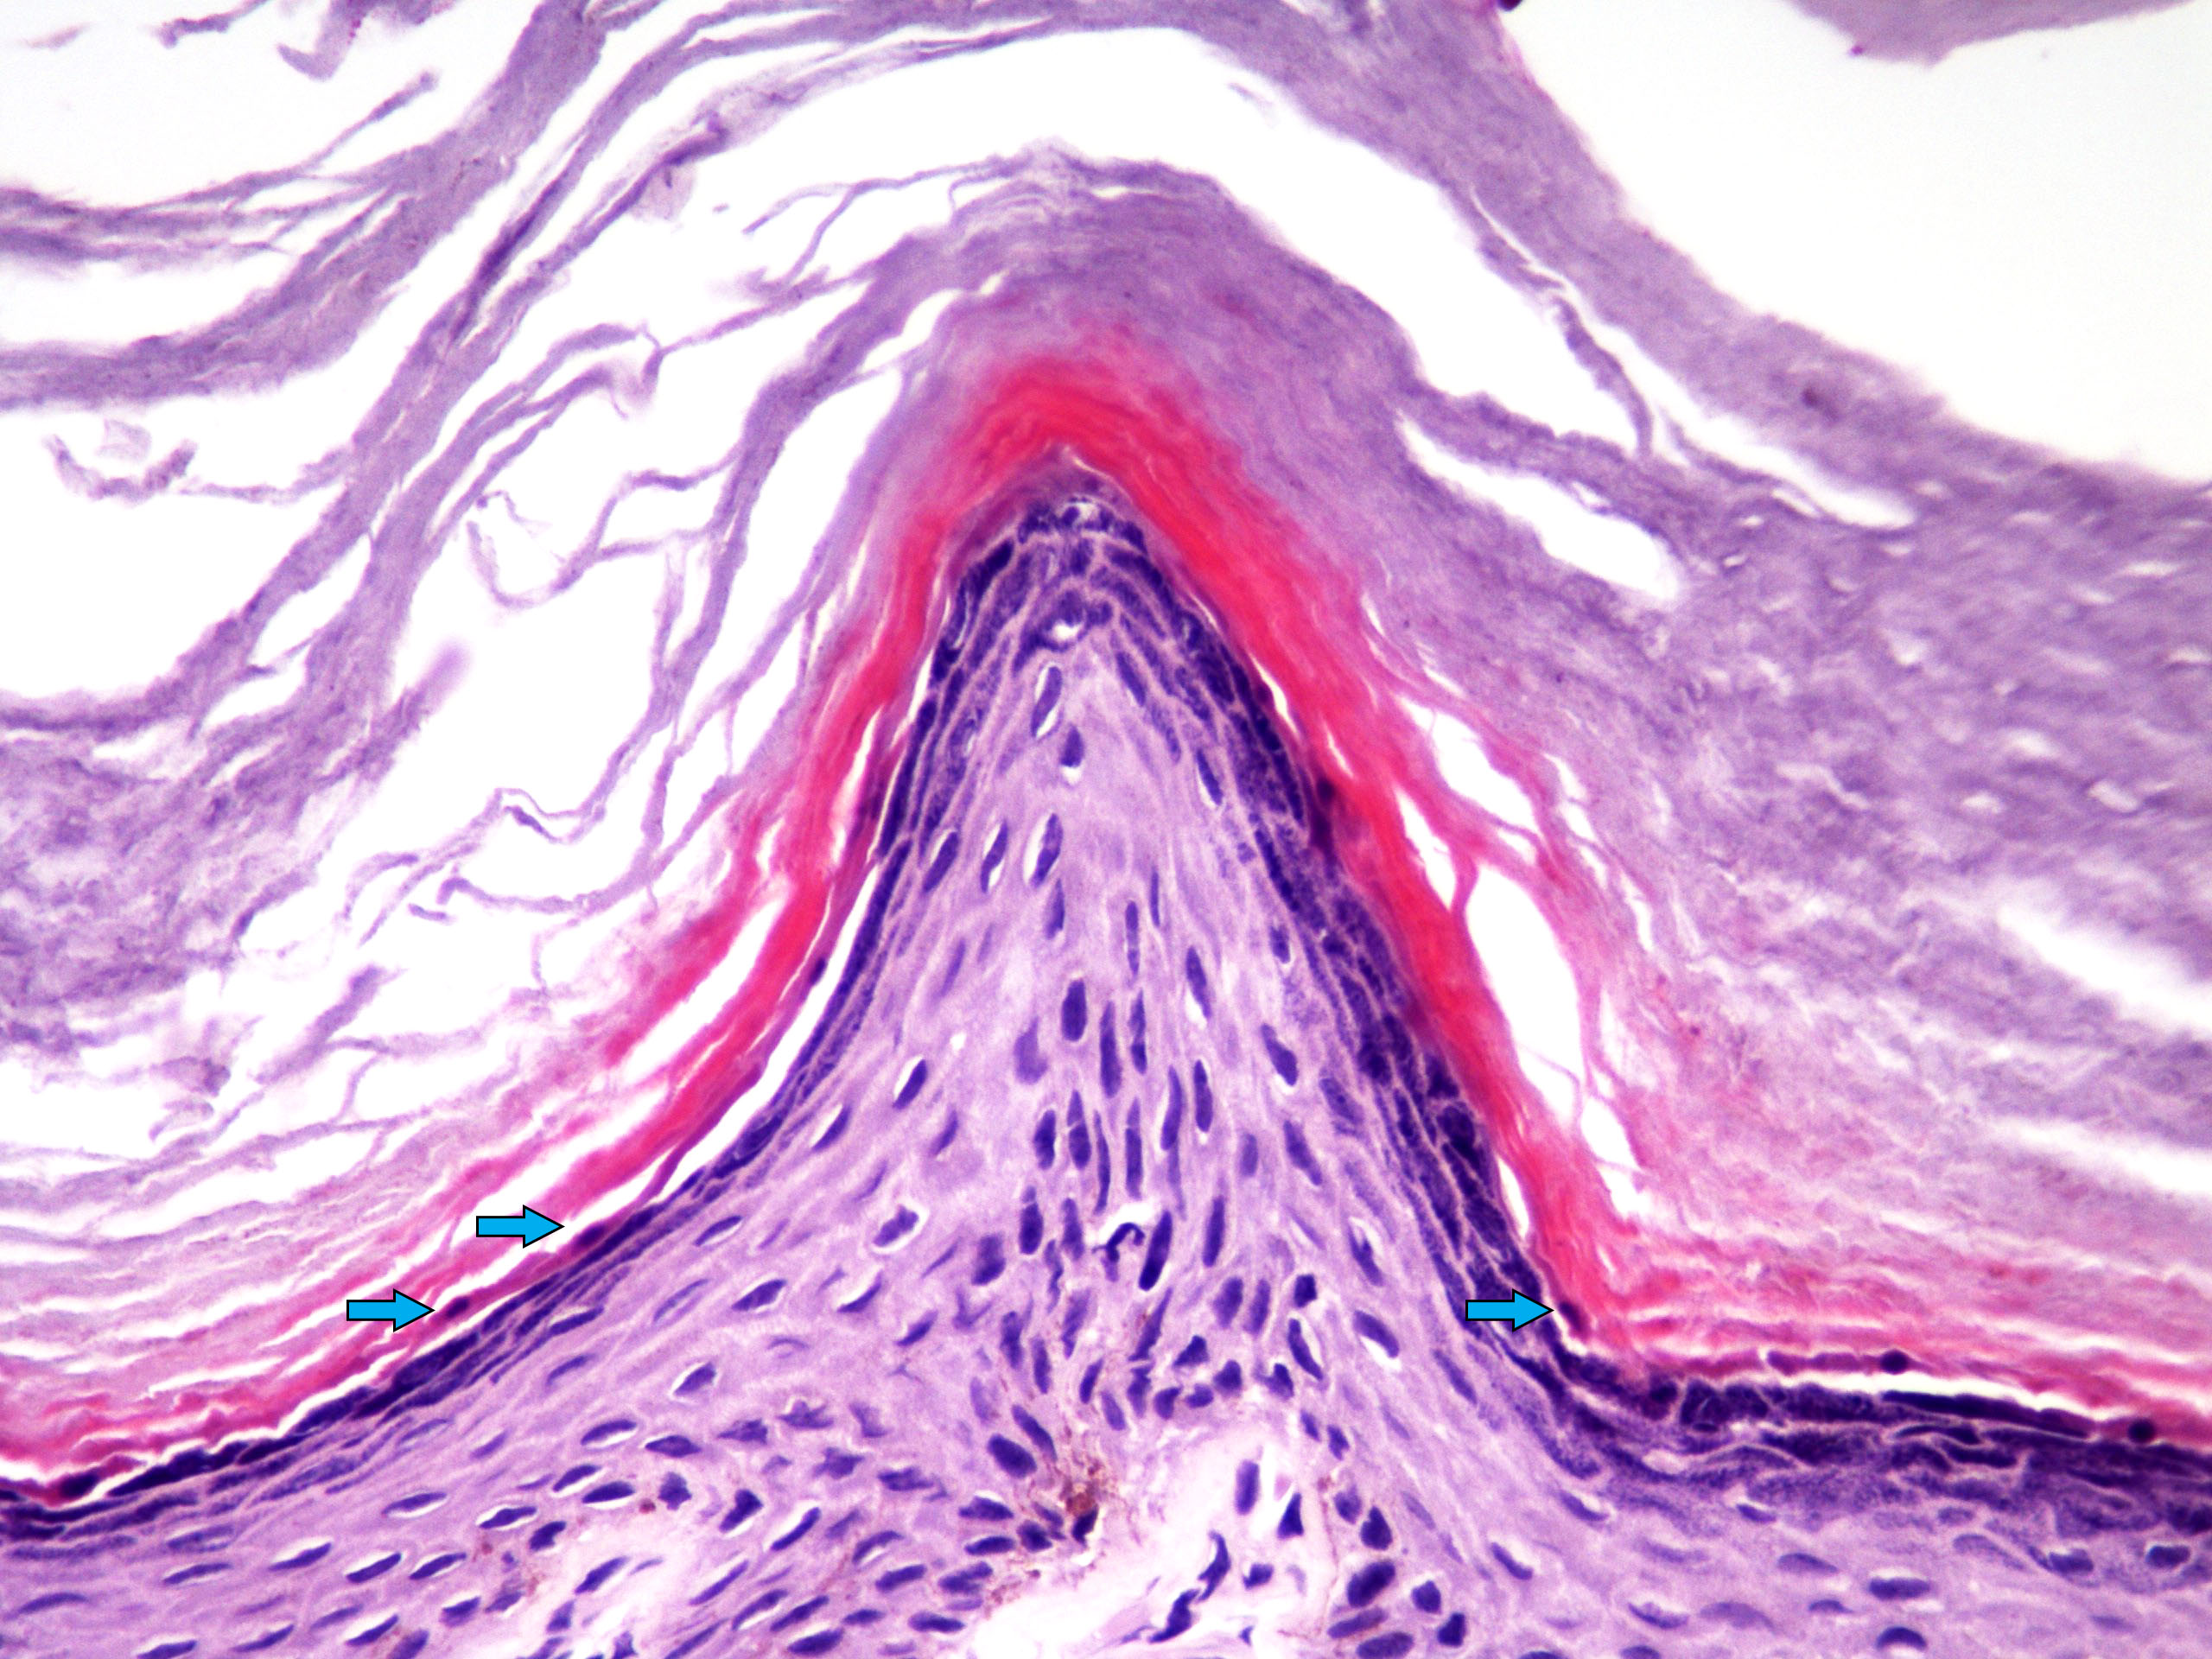

Microscopic (histologic) description

- Acantholysis with characteristic dyskeratosis forming corp ronds and grains

- Corp rond: rounded keratinocyte in superficial spiny and granular layer with basophilic / pyknotic nucleus, perinuclear halo and often a rim of eosinophilic cytoplasm (J Dermatol 2017;44:232)

- Grain: elongated keratinocyte in the stratum corneum with small basophilic nuclei and intensely pink cytoplasm; appears as plump parakeratosis; may form tiers (J Dermatol 2017;44:232)

- Suprabasal acantholysis and clefting with retained single layer of basal keratinocytes overlying dermal papillae which appear to project into the acantholytic cavity (villi) (J Dermatol 2016;43:275)

Microscopic (histologic) images

- Comment: The specimen exhibits parakeratosis, epidermal hyperplasia, acantholytic dyskeratosis with prominent corp rond and grain formation, suprabasal clefting with formation of villi and a mild superficial perivascular lymphocytic infiltrate. Although similar acantholytic dyskeratosis may be seen in a number of entities, given the clinical history of greasy papules in a seborrheic distribution, a positive family history and persistence of lesions, the findings are most consistent with Darier disease.

- Warty dyskeratoma:

- Identical Darier type acantholytic dyskeratosis but solitary lesion

- Tends to have distinct cup shaped epidermal invagination and very prominent villus formation (J Dermatol 2017;44:232)

A. Darier disease. The photomicrograph shows acantholysis with dyskeratosis (corp ronds and grains) as well as the formation of villi classically seen in Darier disease. While Hailey-Hailey disease may have acantholysis with dyskeratosis, prominent corp ronds and grains are lacking. Pemphigus has bland acantholysis and herpes simplex shows distinct viral cytopathic change. Seborrheic dermatitis is a spongiotic dermatitis.